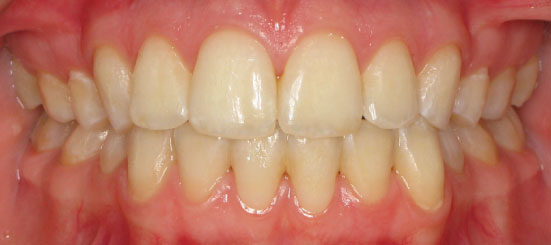

Class I Non-Extraction |